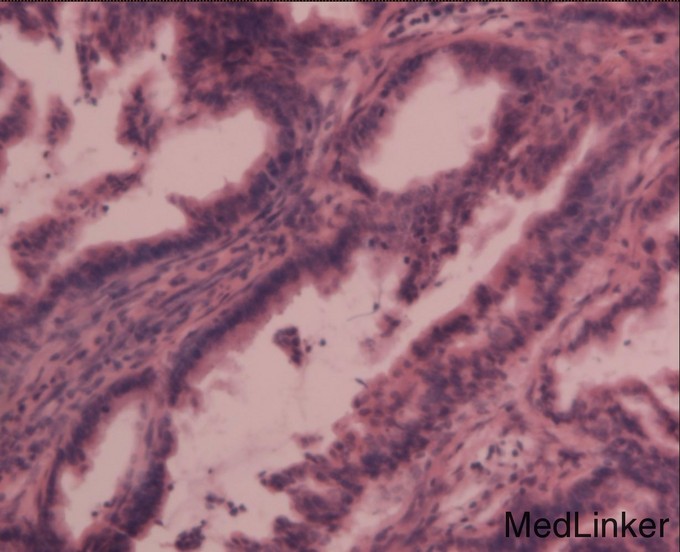

诊断: 胰头占位 恶性可能大 治疗:全麻下手术探查:肝脏於胆改变,无转移结节,腹壁及盆腔未见癌转移,胰头略增大,切开kocher筋膜,游离十二指肠降段,显露胰头后方,触及胰腺钩突2.5×2.0cm质硬肿物,界不清,胆囊无明显增大,约7×4×3cm,肝总管、胆总管全程明显扩张,直径约1.8cm,术中诊断胰腺头部占位,行胰十二指肠切除术,术中冰冻病理及术后病理证实恶性。病理镜下:癌细胞呈不规则腺样,筛网状排列,部分区域见淋巴组织。胰腺腺癌,高分化,肿物周围见少许淋巴结结构,考虑淋巴结受侵及,胃、肠、网膜未见癌,慢性胆囊炎。CD34及D2-40染色未见明显脉管癌栓,S-100染色见神经侵犯。